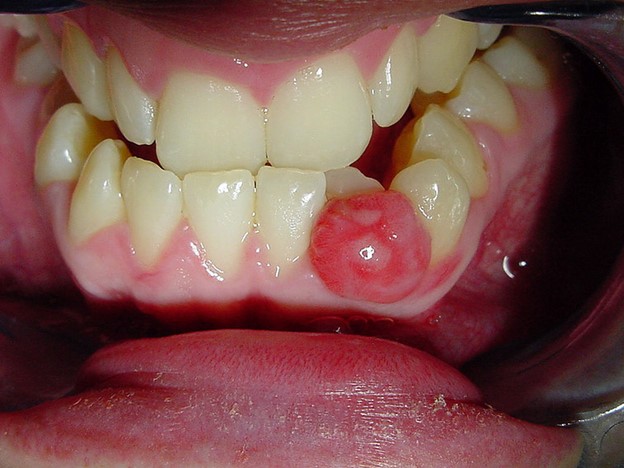

یکی از شاخص های اصلی کیست فک، تورم در ناحیه آسیب دیده است. این تورم ممکن است به صورت یک توده یا برآمدگی قابل مشاهده در امتداد خط فک یا داخل دهان ظاهر شود. این تورم می تواند با حساسیت یا ناراحتی، بویژه هنگام اعمال فشار، همراه باشد.

در برخی موارد، کیست فک ممکن است عفونی شود و منجر به تشکیل یک مجرای سینوسی تخلیه کننده شود. این می تواند منجر به ترشح چرک یا مایع از ناحیه آسیب دیده، همراه با بو یا طعم بد شود. ترشح اغلب نشانه کیست پیشرفته یا پیچیده ای است که به توجه فوری نیاز دارد.